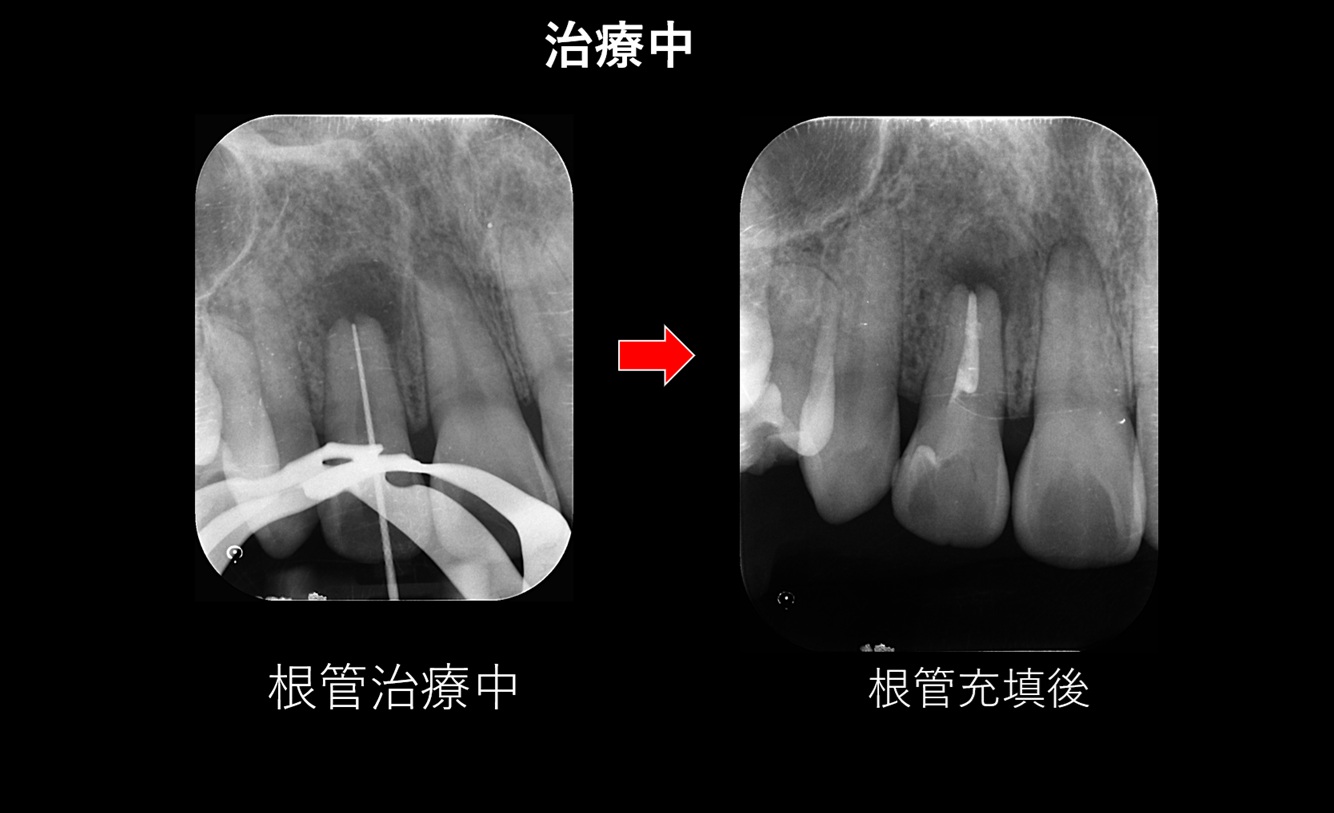

根管内の感染組織の除去と消毒

↑ 専用の根管治療器具を使用して、歯の内部にある感染した歯髄組織を丁寧に除去しました。その後、細菌の増殖を抑える消毒薬を用いて根管内を十分に洗浄・消毒し、根管内に ガッタパーチャポイント と呼ばれる封鎖材料を充填しました。

さらに、生体親和性の高い MTAセメントシーラー を併用し、根管内を緊密に封鎖しています。